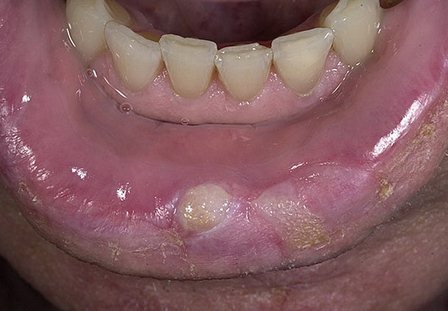

В первую очередь на появление «вражеских» клеток реагируют подбородочные лимфоузлы, воспаляясь и становясь подвижными. Их можно легко заметить, ощупывая нижнюю челюсть. Далее на поверхности нижней губы возникает припухлость, которая слегка зудит и имеет плотную консистенцию. Даже если у вас появятся эти симптомы рака губы, скорее всего вы не обратите на это внимание и примите за простуду. В это время в центре припухлости уже образовалась язвочка с валикообразным краем, имеющая нечеткие границы. В центре этой язвочки – корочка, которая безболезненна сама по себе, но при удалении может вызывать боль. Если убрать эту корочку, то можно увидеть кровоточащее основание, образованное бугорками.